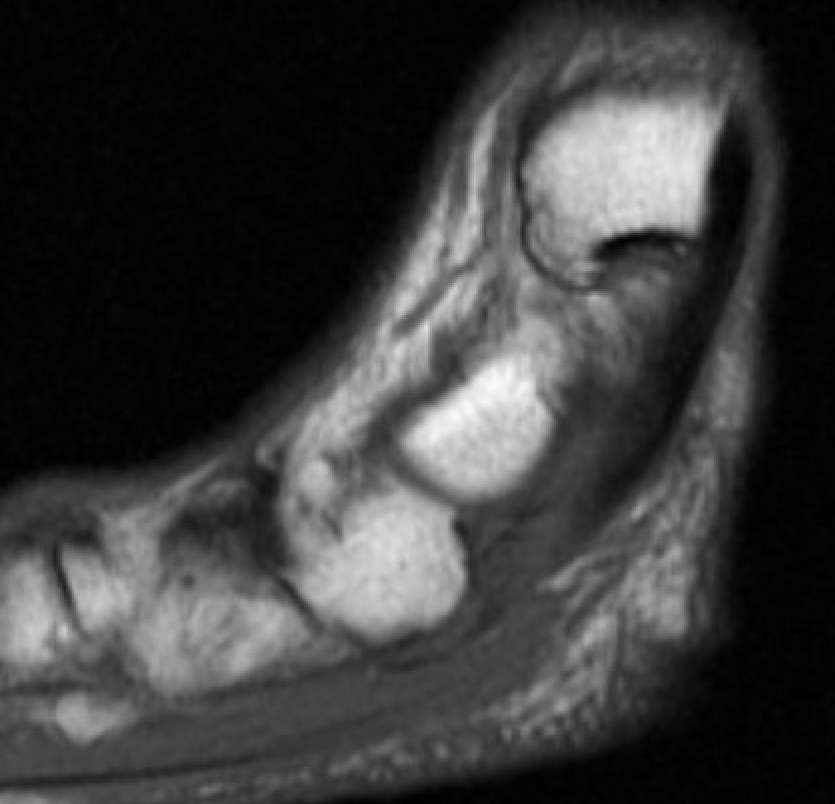

MRI

Tendonitis - fluid around tendon

Tendinopathy - tendon thickening

Tears

Tibialis posterior tendonitis

Tibialis posterior tendinopathy